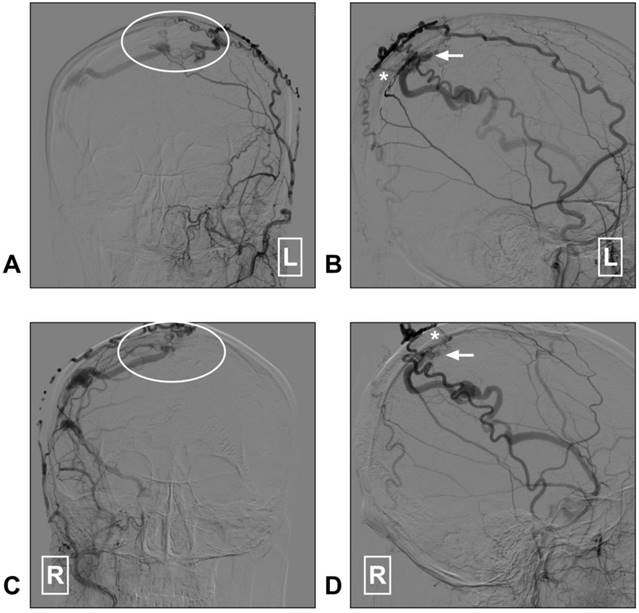

Figure 5

STA supplied superior sagittal sinus DAVF. A: Angiogram of the left ECA in AP view shows a superior sagittal sinus DAVF (white ellipse); B: Angiogram of the left ECA in lateral view shows the transosseous branches (asterisk) of the STA feed the DAVF. The arrow indicates the fistula point. C: Angiogram of the right ECA in AP view shows a superior sagittal sinus DAVF (white ellipse); D: Angiogram of the right ECA in lateral view indicates the fistula point (arrow). The transosseous branch (asterisk) of the right STA also feeds the DAVF. Abbreviation: AP: anterioposterior; DAVF: dural arteriovenous fistula; ECA: external carotid artery; L: right; R: right; STA: superficial temporal artery.

(4). Dural arteriovenous fistula

DAVF is an arteriovenous shunt located in the dural wall. The meningeal branches of the ECA and ICA are the main feeding arteries in DAVFs, with the middle meningeal artery (MMA) and OA the most commonly involved [82-84]. Occasionally, the STA can be involved in a DAVF. The location of fistula point in STA supplied DAVFs could be at the superior sagittal sinus, the transverse-sigmoid sinus, the anterior cranial fossa, or the tentorial region [6, 84-89]. When the STA serves as the main feeding artery, it can become swollen and thick [90, 91].

Currently, in DAVF embolization, the STA is known to be poorly suitable because a pressure gradient of its transosseous branches may limit embolic agent penetration toward the shunt point [92, 93]. Recently, dual-lumen balloon has been proposed as a useful tool that may help to facilitate the penetration of liquid embolic agents from the STA [94]. However, DAVF embolization via the STA is not a completely safe path and it carries the risk of cast extrusion [95]. A DAVF case with STA as the feeding artery is described in Figure 5.